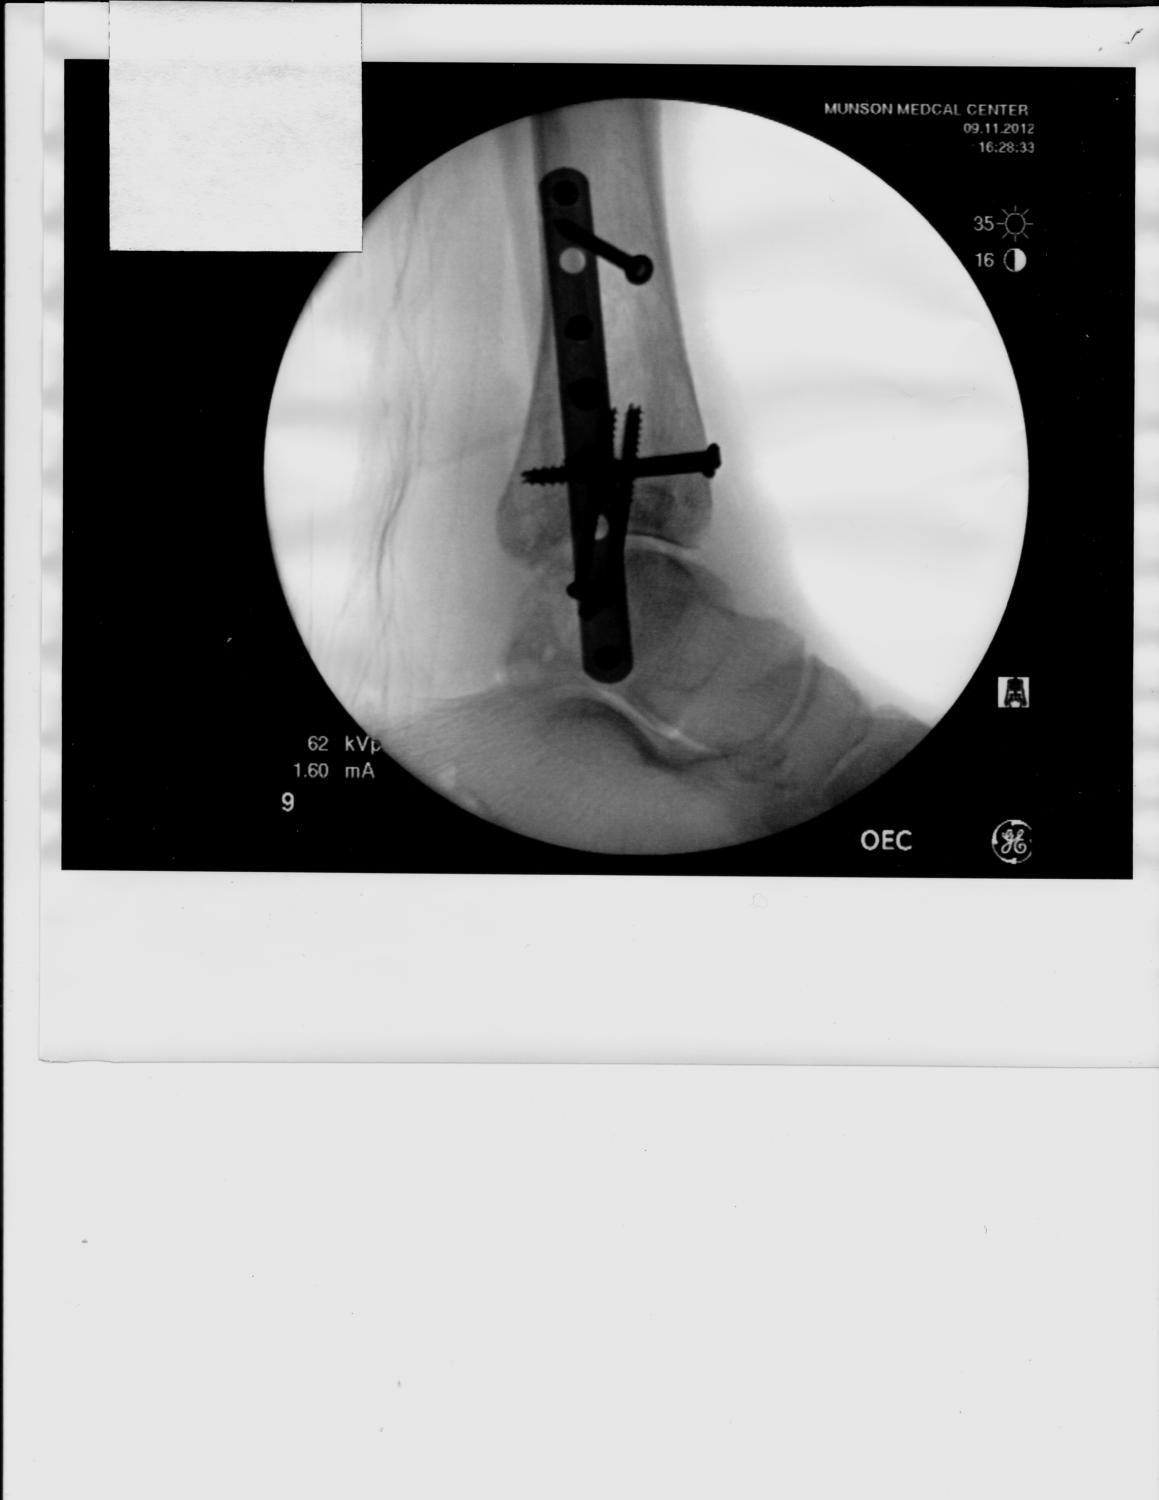

DH is home from hospital after only one night. 4" plate and 10 screws, ginormous splint that prevents his leg from bending goes halfway up his thigh. Two weeks of this it looks like, then, HOPEFULLY, a cast below the knee, then... well, it seems to go on and on ...

The one long screw in the left picture has more fractures in that ankle than they could count. The good news is that the joint looks good. So far the skin has held up. Another appointment in a week.